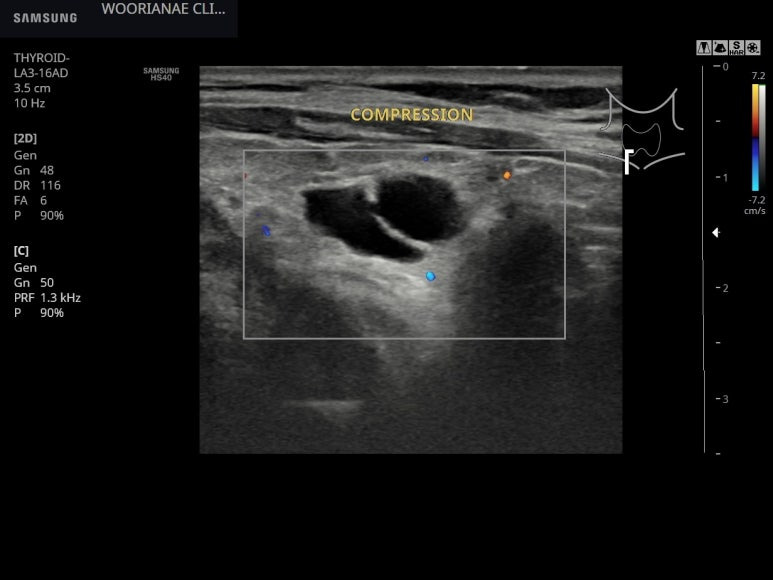

눌러보면 눌리지는 않으나.. 낭종으로 생각되며